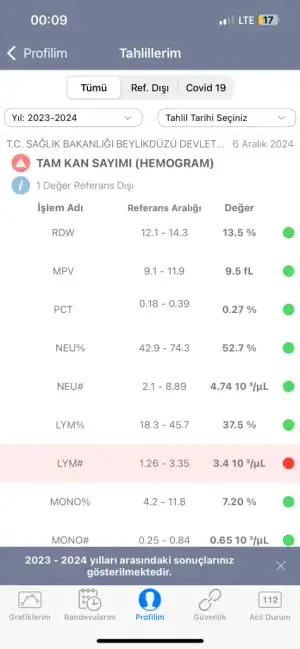

Merhaba bugün kadın hastalıkları ve doğum bölümüne gittim rahim ağzında yara var diye ve bana yakma önerdiler bi kaç test yaptılar anestezi için ve sonuçları pazartesi göstericem ama sonuçlar çıktığı için merak ediyorum aranızda anlayan veya doktor olan biri varsa cevaplayabilirmi rica etsem?

IMG_8035.webp32,3 KB · Görüntüleme: 115

IMG_8035.webp32,3 KB · Görüntüleme: 115 -

IMG_8036.webp32,2 KB · Görüntüleme: 112

IMG_8036.webp32,2 KB · Görüntüleme: 112 -

IMG_8037.webp20,9 KB · Görüntüleme: 115

IMG_8037.webp20,9 KB · Görüntüleme: 115 -

IMG_8038.webp21,8 KB · Görüntüleme: 104

IMG_8038.webp21,8 KB · Görüntüleme: 104 -

IMG_8039.webp21,3 KB · Görüntüleme: 108

IMG_8039.webp21,3 KB · Görüntüleme: 108 -

IMG_8040.webp18 KB · Görüntüleme: 105

IMG_8040.webp18 KB · Görüntüleme: 105 -

IMG_8041.webp20,9 KB · Görüntüleme: 101

IMG_8041.webp20,9 KB · Görüntüleme: 101 -

IMG_8042.webp40,6 KB · Görüntüleme: 115

IMG_8042.webp40,6 KB · Görüntüleme: 115